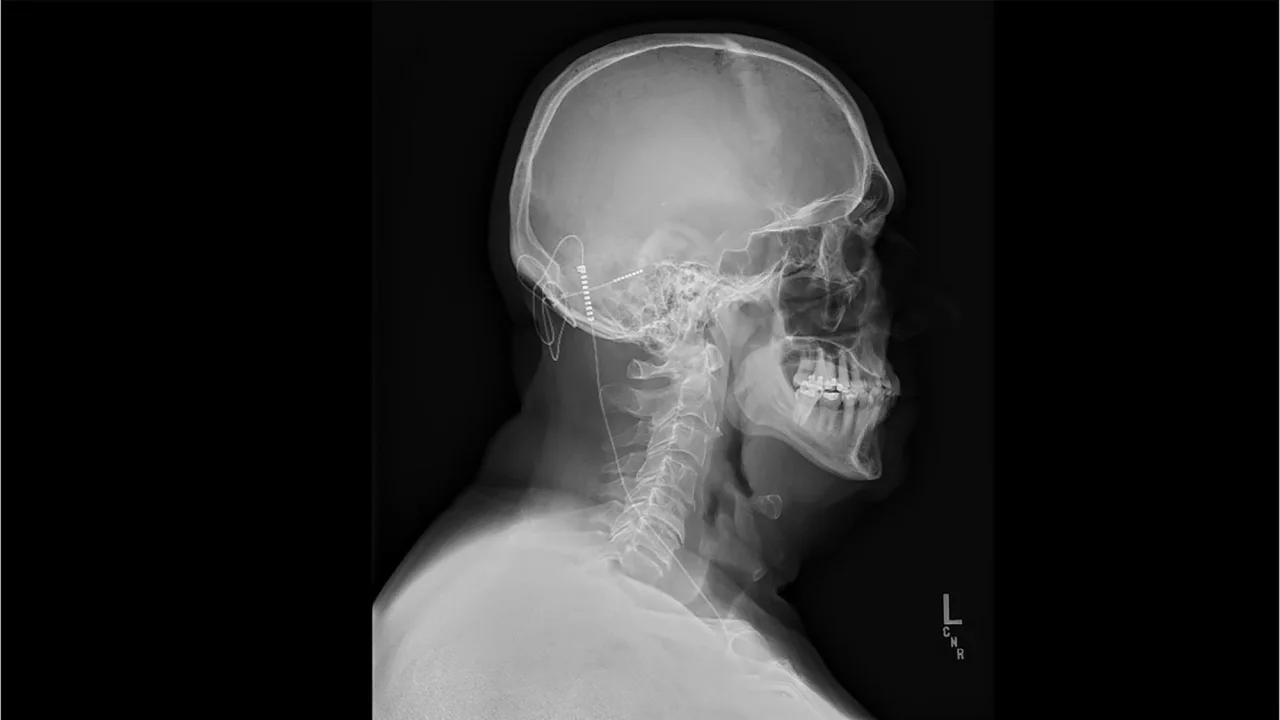

Nicholas’ surgery involved placing an electrode, a wire, in the cerebellum, at the back of his brain. Doctors connected the wire to a small device under the skin of his chest.